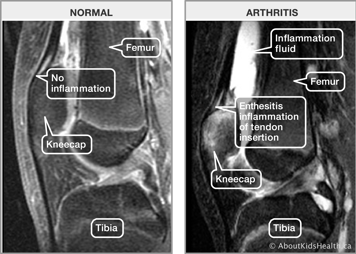

Below is an X-ray of a normal knee joint versus an arthritic knee joint. The knee on the right shows the effects of arthritis. Inflammation and increased blood flow to the joint causes bone overgrowth, decreased joint space and decreased bone density (bone appears not as white in an X-ray, which means that it is less dense. This is called osteopenia).